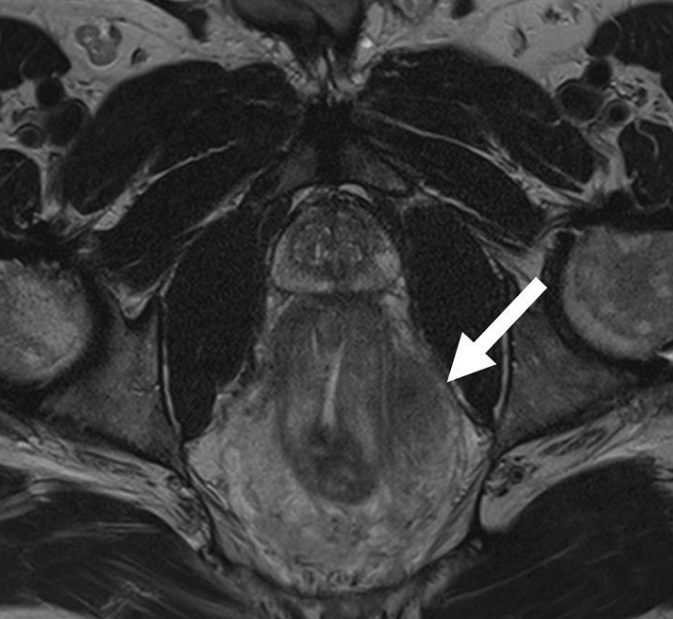

В исследовании участвовали 197 человек с диагнозом оспа обезьян. Средний возраст 38 лет. Все – мужчины. При этом подавляющее большинство (кроме одного человека) заявили, что имеют сексуальные контакты с представителями своего пола. У половины выявлено поражение гениталии (56% ) и анальной области (41%). О болях в прямой кишке сообщили 36% инфицированных, у 15% появился отёк полового органа.